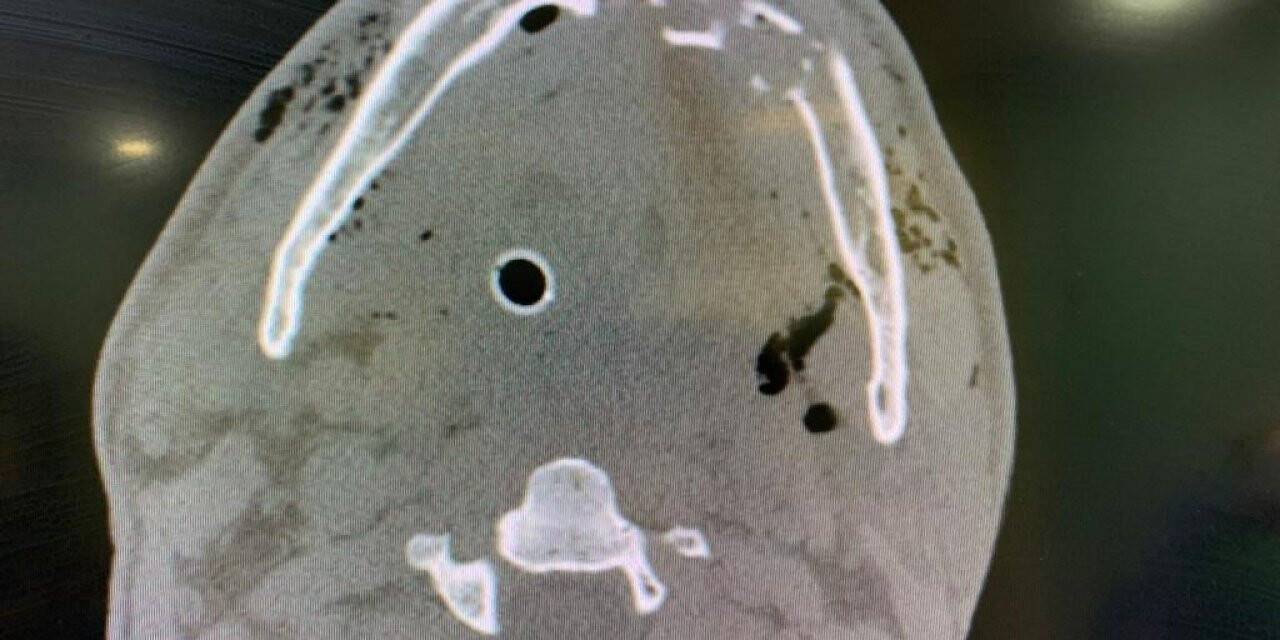

Silahla yaralanan Tarkan Özer’e hayata döndüren müdahale